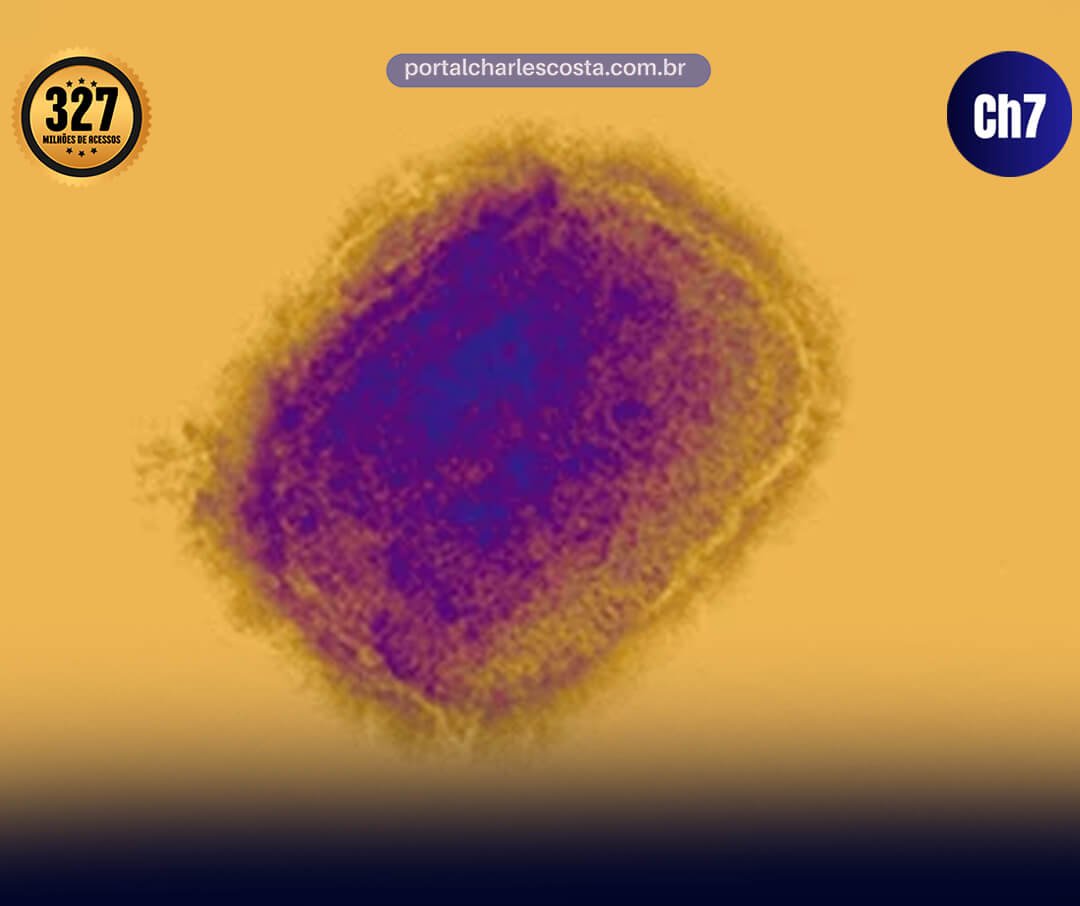

Características da variante clado Ib

O clado Ib é uma ramificação do clado I do vírus MPXV, associado a surtos na República Democrática do Congo e países vizinhos desde 2024. Diferente do clado II (responsável pelo surto global de 2022, com letalidade baixa), o clado I tende a quadros mais graves em contextos endêmicos, com transmissão por contato próximo, incluindo vias sexuais, e potencial para lesões mais extensas. A Organização Mundial da Saúde (OMS) classificou a mpox como emergência de saúde pública internacional devido à disseminação dessa variante na África Central.